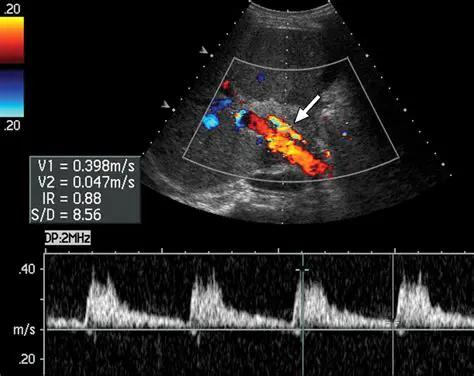

Doppler Ultrasound in Liver Disease